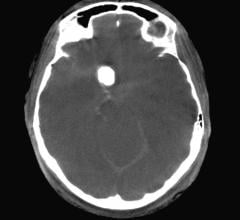

December 12, 2018 — In stroke, time saved on imaging is time gained in the treatment window. The recently updated ...